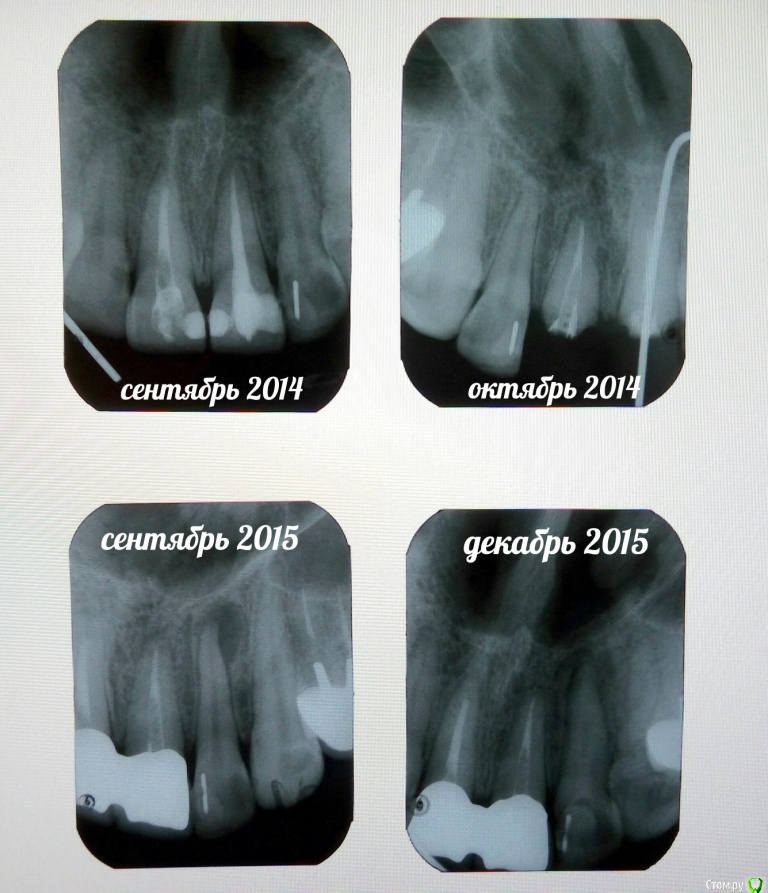

Иноземцева Опубликовано 19 декабря, 2015 Автор Поделиться Опубликовано 19 декабря, 2015 Сегодня была на консультации у другого ортопеда, сделала прицельный снимок. Он сказал,что каналы на передних единицах плохо запломбированы, плохое сцепление коронки с культей зуба (возможно она была не правильно обточена), необходимо их пролечить заново,сделать культевые вкладки, отлить новые коронки и их устанавливать.Старые коронки нельзя просто снова посадить на цемент. Но боюсь, что врач у которого я ставила коронки не пойдет на это... Т.к. он мне сказал, что могу ходить,пока коронки сами не отвалятся (не обращая внимания что появился запах и десна кровоточат), а потом он просто их снова "приклеит". Подскажите пожалуйста, как быть в данной ситуации и что я могу требовать у врача? На фото примерная хронология установления коронок. Видно ли из снимка,что тот врач сделал свою работу не качественно? Огромное спасибо всем ответившим! Ссылка на комментарий

M@estro Опубликовано 19 декабря, 2015 Поделиться Опубликовано 19 декабря, 2015 Требовать от врача никогда ничего не надо - это бесполезно и , более того, может привести к ухудшению клинической ситуации. P.s. Судя по снимку "октябрь 2014" и сравнении его со снимком "сентябрь 2014" - зубы просто уничтожены бором. Надо обратиться к квалифицированному специалисту за помощью, который проведет очный осмотр с целью оценки функциональной ценности зубов. Объективный осмотр предпочтительнее снимков в этом аспекте. 1 Ссылка на комментарий